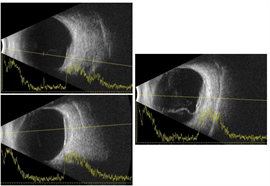

Optical coherence tomography through the macula of the right eye demonstrated a clear vitreous, normal retinal laminations, and mild irregularity of the retinal pigment epithelium band within the fovea. There was no intraretinal or subretinal fluid. There was thickening and consolidation of the submacular choroid with hyporeflective lamellae within the lesion and no normal choroidal vasculature visible in this area. B-scan ultrasonography demonstrated a plaque-like, hyperechoic choroidal lesion with shadowing posterior to the lesion.